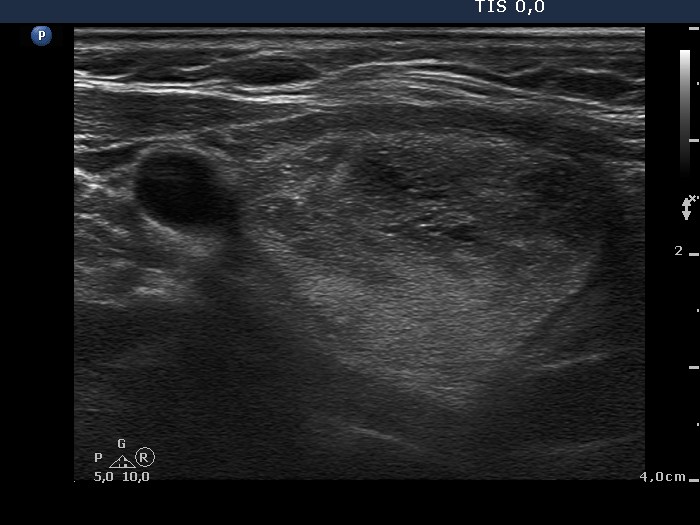

Follow-up investigation two years later (ultrasonographic picture 9)

Right lobe, longitudinal scan